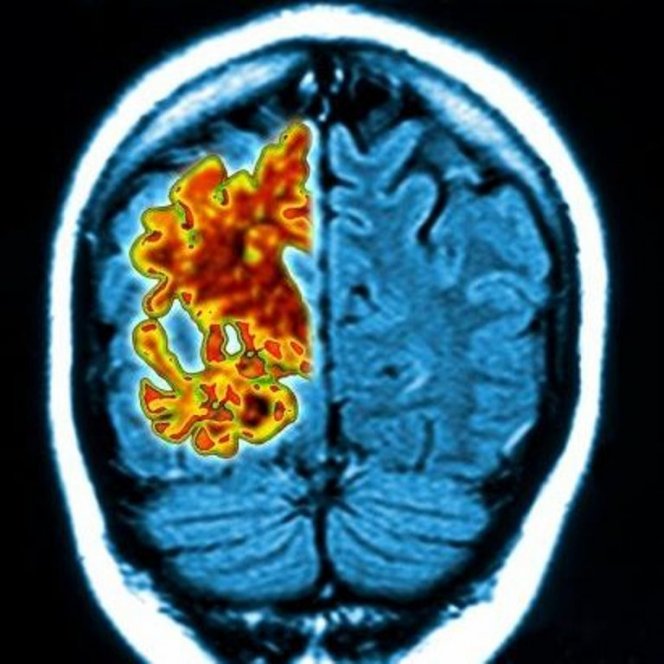

Развитие болезни Альцгеймера можно остановить с помощью инъекций в центры памяти мозга. Они активизируют генетические процессы, очищающие мозг от деструктивных бета-амилоидных бляшек, как полагают ученые из Имперского колледжа Лондона.

Четыре года тому назад ученые обнаружили, что белок под названием PGC1 -alpha является жизненно важным в деле предотвращения скоплений бета-амилоидных бляшек в мозге. У людей с болезнью Альцгеймера он не производится в достаточных количествах. Исследователи доказали возможность проведения инъекций, вызывающих образование данного белка, прямо в мозг.

Безвредный вирус подвергся редактированию для того, чтобы в него включили ген, который инфицировал клетки мозга и переписал их генетический код для производства большего количества белка, сражающегося с бляшками. Инъекции проводились в области гиппокампа и коры мозга, отвечающие за процессы формирования памяти и ориентации - именно эти зоны первыми страдают при болезни Альцгеймера.